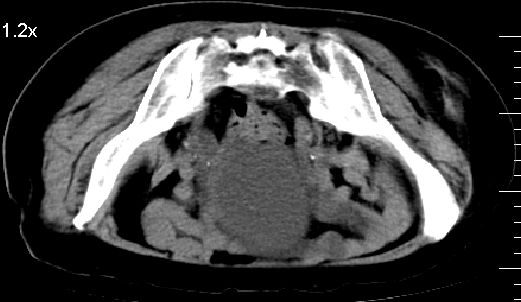

膀胱充盈可,壁光滑厚薄尚均匀,其内下方可见不规则的致密影,建议做膀胱镜检查

膀胱癌突破浆膜可能性大

膀胱三角区不规整软组织改变,双侧输尿管扩张,所以占位性病变肯定首先考虑,建议改变体位扫描除外游离血块影,但老年人出血原因一定要查明。

双侧输尿管下端扩张,并膀胱内血凝块 输尿管下端结石